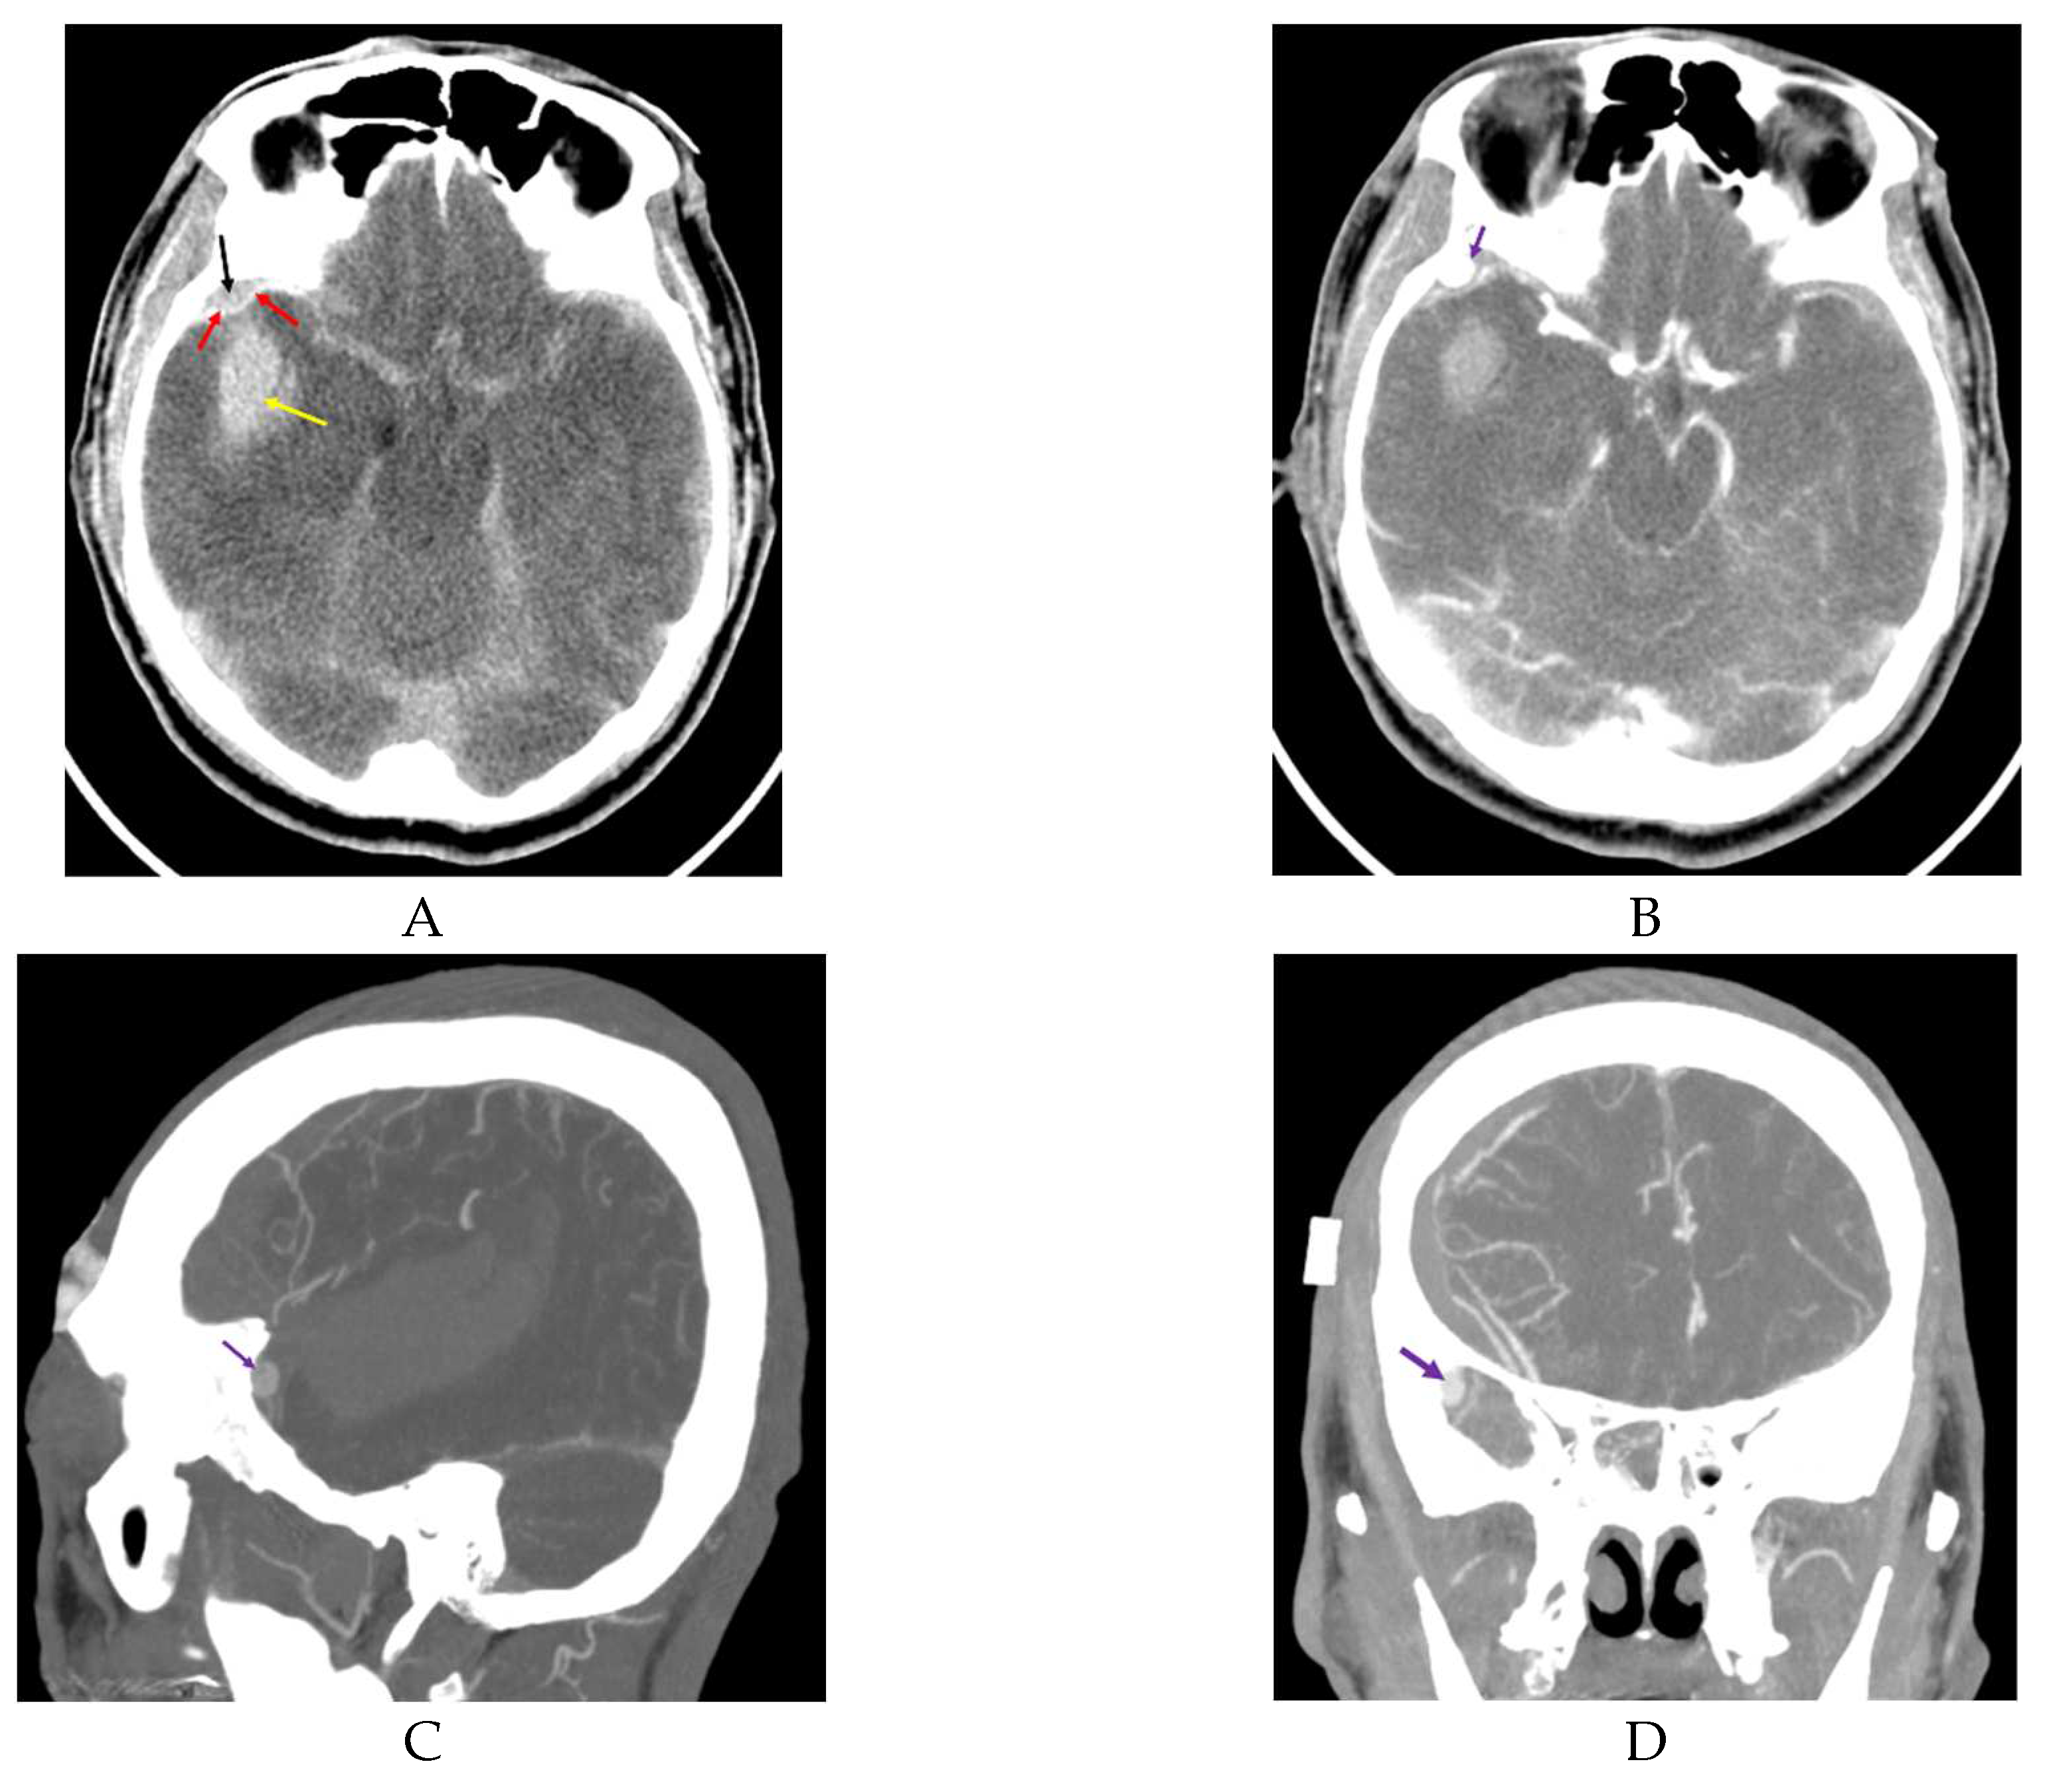

Rumbaugh et al., suggested that SDH or ICH may result from the rupture of a pseudoaneurysm in the MMA, particularly if the dura has been torn; however, they did not present a case of dura tear resulting in ICH [16]. Kumar et al., and Moon et al., reported cases with acute small EDH and ICH from rupture of a pseudoaneurysm in the MMA after trauma [6,7] (Figure 1).

In both reports, the authors mentioned that brisk epidural bleeding during bone flap removal and dura tear were detected. Moon et al., proposed that a rupture of a pseudoaneurysm rupture in the MMA contacting with a dural defect could cause ICH via the dura tear [6] (Figure 2). Figure 1 and Figure 2 demonstrate that rupture of a pseudoaneurysm in the MMA with a dura tear results in small EDH and acute ICH. In situations where there is a dura tear, rupture of a pseudoaneurysm located in the epidural space produces EDH at the initial stage of the rupture and subsequently results in ICH via the dura tear.

Figure 1. Preoperative computed tomography (CT) before (A) and after (B, C, D) contrast injection. Pre-contrast CT demonstrates a small epidural hemorrhage and intracerebral hemorrhage (black arrow, epidural hemorrhage; red arrow, dura mater; yellow arrow, intracerebral hemorrhage). Post-contrast CT (B, C, D) shows a suspicious pseudoaneurysm located in the epidural space (violet arrow: suspicious pseudoaneurysm).